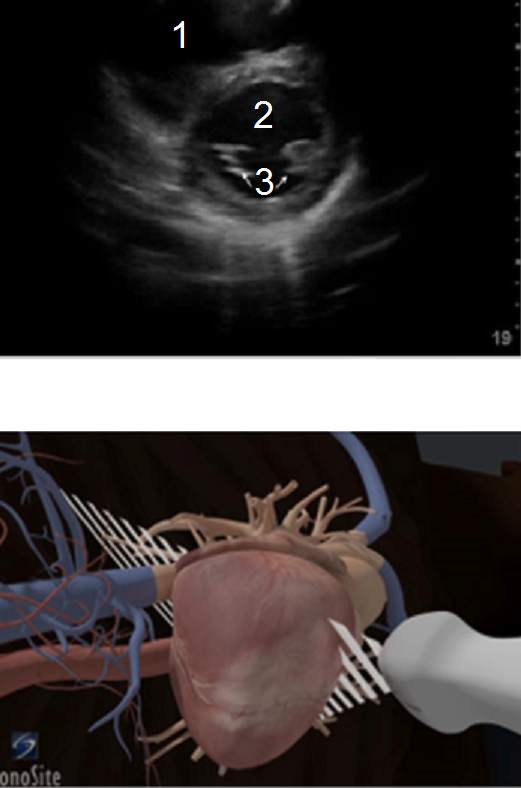

RUSH 胸骨旁短轴视图图像

右心室 (RV)

左心室 (LV)

乳头肌